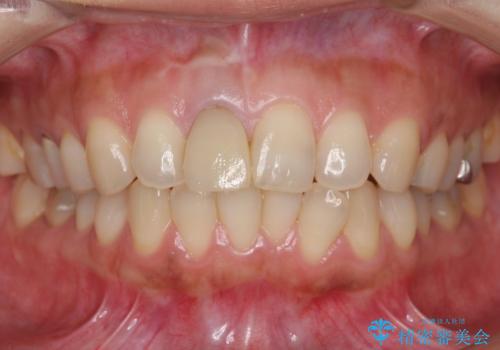

差し歯をもっと自然に 30代女性

- もっと自然にみえるような差し歯にしたいと希望され来院された患者様です。

患者様の天然歯はグラデーションがあり切縁(歯冠の先端)はやや透けていて透明感があるのに対し、前歯(右上1)の差し歯はやや黄色く不透明で単調な色味でした。

前歯のクラウンは一度修正し、患者様の理想とする色味や形態を追求しました。

天然歯と見紛うほどの自然な仕上がりに喜んで頂けました。

ジルコニアクラウンの繊細なグラデーション・透明感は熟練した技工士さんの技術の賜物です。

右上1:ジルコニアクラウン スペシャル

右上5:ジルコニアクラウン スタンダード